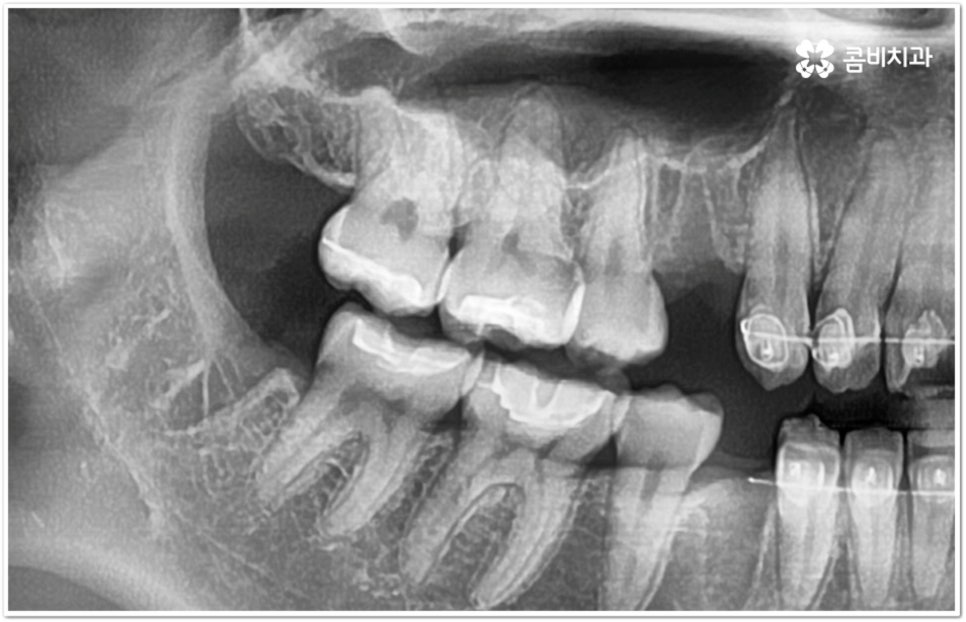

만약 똑바로 자라나고 관리가 용이하며 마주보는 대합치 역시 정상적으로 맹출되었다면 사랑니를 꼭 발치할 필요는 없을 거예요. 그러나 보통 사랑니는 사람의 치아 중에 가장 마지막에 나오는 치아라서 이미 구강 내 공간이 비좁은 상태이기 때문에 비스듬하게 자리를 잡고 일부분만 맹출이 되는 경우가 많이 있어요. 보통 머리가 앞쪽으로 기울어진 근심위로 자리잡는 케이스가 가장 많으며 그 밖에도 치아 머리가 뒤쪽으로 기울어져 있거나 혀쪽, 볼쪽으로 누운 케이스, 아예 옆으로 완전히 누운 케이스 등도 발견되고 있는데요.

잇몸에 반쯤 덮힌 채로 삐뚤게 나온 사랑니는 칫솔질을 제대로 하기 어렵고 위생 관리가 잘 되지 않아 주변 잇몸에 염증이 생기기 쉬우며 어금니까지 충치가 번질 위험이 높아지게 되어 구강 건강 관리 및 예방 차원에서 발치 처치를 해주실 필요가 있어요. 발치 난이도는 사랑니의 경사 각도와 방향 및 치아 뿌리의 길이와 개수, 사랑니 뒤쪽 턱 뼈의 각도 및 형태, 하치조 신경 또는 상악동까지의 거리 등에 따라서 달라질 수 있습니다.

이때 아래사랑니발치 의 경우 아래턱 부근을 지나가는 큰 신경인 하치조 신경을 건드리지 않고 조심스럽게 사랑니만 제거해야 하기 때문에 3D-CT 등 정밀 검진 기계를 통해 사랑니의 매복 위치, 깊이, 각도 등의 상태와 신경까지의 거리 등을 먼저 꼼꼼하게 파악한 후에 발치를 해 줄 필요가 있는데요. 만약 완전히 매복되어 있다면 사랑니 주변에 함치성 낭종이 발생할 수도 있는데 이로 인해 주변 치조골이 파괴되고 어금니 쪽으로 병변이 확산되면 결국 치아를 상실하게 되거나 턱뼈가 약해져서 작은 충격에도 부러지는 현상이 발생할 가능성도 있으므로 될 수 있는대로 치료 시기를 놓치지 않는 것이 중요한 포인트라고 할 수 있어요.

이와 같이 환자분들의 상황에 따라서 잇몸 절개 및 골삭제 후 사랑니를 조각내어 빼내야 하는 고난도의 과정들이 필요할 수도 있기 때문에 아래사랑니발치 시 관련 임상 경험이 많고 섬세한 기술력을 가지고 있는 숙련된 의료진과 함께 하시길 권유드리고 있습니다.

아래사랑니발치 와 다르게 윗 사랑니 발치 시에는 상악동까지의 거리가 너무 짧을 경우 천공 및 감염의 위험이 있으니 이에 대해서 3D CT 를 통해 꼼꼼하게 확인하고 환자분들의 상황에 맞는 치료를 진행할 필요가 있어요. 예를 들어 사랑니로 인한 문제가 크지 않은 경우 그대로 두고 지켜볼 수도 있고 다른 치료를 하는 중에, 즉 교정이나 임플란트 등을 진행하는 과정에서 발치가 꼭 필요한 경우라면 상악동 거상술, 뼈이식 등의 치료를 선행하여 무리하지 않게 뽑아주는 것이 좋을 거예요.

관리하기 까다롭기 때문에 위 아래사랑니발치 를 해 주는 것이 보통이긴 하지만 간혹 사고로 어금니를 상실하거나 유전적으로 어금니가 없으신 분들의 경우 교정 치료를 통해 어금니 대신 사용하는 사례가 있으니 필요하다면 발치 결정 전에 꼼꼼하게 검진을 받아보실 필요가 있어요.

모든 경우에 사랑니가 어금니를 대신할 수는 없으며 사랑니로 어금니를 대체하기 위해서는 사랑니의 상태, 이동 가능 공간, 주변 구조물 및 전체 구강 구조 등 환자분들의 상황을 먼저 면밀하게 살펴본 후 교정 치료 계획을 세심하게 세워 잇몸과 사랑니의 손상 없이 치료할 필요가 있으므로 고난도 과정에 맞게 술자의 높은 숙련도가 요구되는 만큼 노하우가 풍부한 의료진을 선택하시길 권유드리고 있습니다.